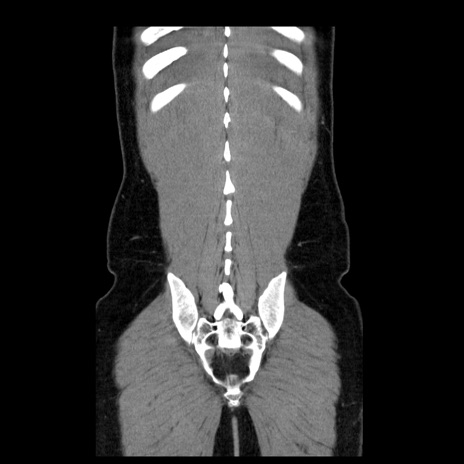

症例4(冠状断像)

【症例】30歳代男性

【主訴】腹痛、嘔吐

【現病歴】昨晩から突然の腹痛あり、その後嘔吐、軟便も出現。腹痛が改善しないため救急搬送となる。2日前にしめ鯖の食事歴あり。

【身体所見】意識清明、苦悶様、BP 135/90mmHg、BT 35.7℃、腹部:平坦、やや硬、心窩部〜臍部に自発痛、圧痛あり、筋性防御+、反跳痛-

【データ】WBC 8100、CRP 0.57